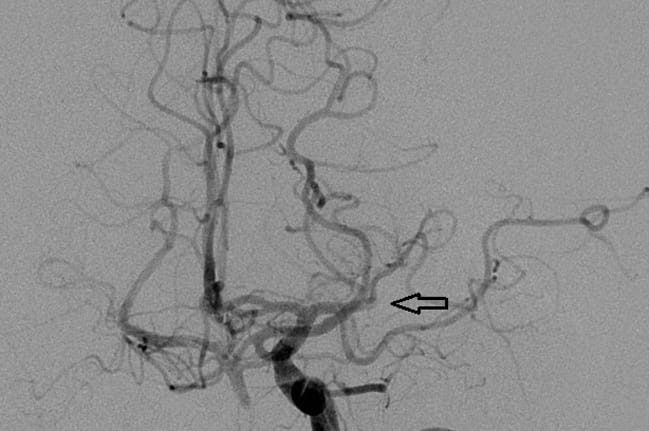

Endovascular Thrombectomy

Endovascular removal of clots proven successful in clinical stroke trials.